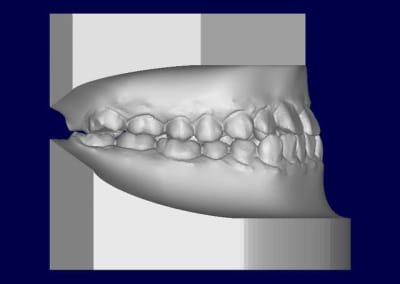

Patient asiatique, 25 ans, consulte car il veut corriger son crossbite bite antérieur localisé aux latérales et son crossbite secteur 2/3. Il aimerait également corriger son apparence générale, son profil notamment.

Classe III squelettique et dentaire.

Ci joints photos, ceph, modeles.

A la mandibule quasiment besoin de ne rien faire, pas besoin de faire de décompensation des incisives leur axes étant quasiment idéal.

Tout la compensation dento alvéolaire se situant au maxillaire chez se patient

il y'a une forte compensation alveolaire maxillaire superieure anterieurement et lateralement,